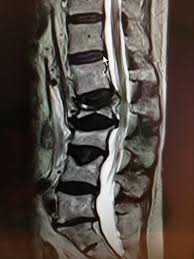

Rezidiv Bandscheibenvorfall Nach Op Dr Christopoulos